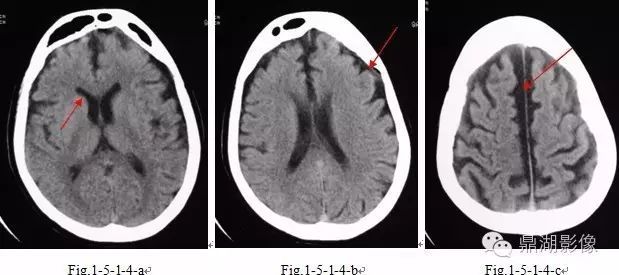

脑萎缩ct图片 (第1页)

脑萎缩ct图片

脑萎缩ct图片解说

脑萎缩ct表现

脑萎缩ct